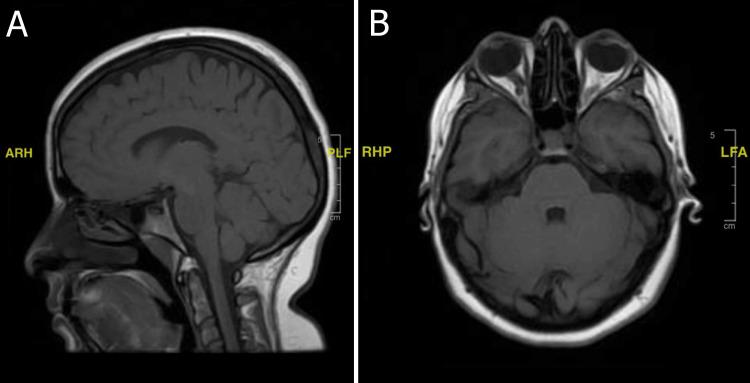

Idiopathic intracranial hypertension (IIH) and multiple sclerosis (MS) are rare neurological disorders that largely affect females within the reproductive age group. The clinical pictures of both diseases can overlap, which therefore places great importance on accurately studying and reporting their concurrence. Therein, we report a case of IIH presenting and progressing simultaneously with MS. This young, previously healthy female presented with the primary complaint of a severe right-sided headache associated with blurred vision and a finding of papilledema. The initial investigations including a lumbar puncture (LP) that revealed high opening pressure (more than 25 mm HO) with normal cerebrospinal fluid (CSF) analysis led to an impression of idiopathic intracranial hypertension, and she was treated accordingly with acetazolamide and scheduled for regular follow-ups with both neurology and neuro-ophthalmology. However, about two months after the initial presentation, she complained of unusual headaches, and a neuro-ophthalmology clinical evaluation revealed complete right homonymous hemianopia, suggesting a lesion in the left temporo-parietal occipital region. The patient was thus admitted as a case of cerebral edema following an urgent brain magnetic resonance imaging (MRI). After obtaining thorough imaging and workup, the patient was given steroids and markedly improved, favoring a diagnosis of tumefactive MS with IIH.

特发性颅内高压(IIH)和多发性硬化症(MS)是罕见的神经系统疾病,主要影响育龄期女性。这两种疾病的临床表现可能重叠,因此准确研究和报告它们的并发情况非常重要。在此,我们报告一例IIH与MS同时出现并进展的病例。这位年轻且此前健康的女性以严重的右侧头痛伴视力模糊为主诉就诊,检查发现视乳头水肿。初步检查包括腰椎穿刺(LP),结果显示初压高(超过250mmH₂O),脑脊液(CSF)分析正常,由此得出特发性颅内高压的印象,她接受了乙酰唑胺治疗,并安排定期接受神经科和神经眼科的随访。然而,在初次就诊约两个月后,她抱怨出现异常头痛,神经眼科临床评估发现完全性右侧同向性偏盲,提示左侧颞顶枕区有病变。因此,在紧急进行脑部磁共振成像(MRI)后,该患者以脑水肿病例入院。在进行全面的影像学检查和评估后,患者接受了类固醇治疗,病情明显改善,支持肿瘤样MS合并IIH的诊断。